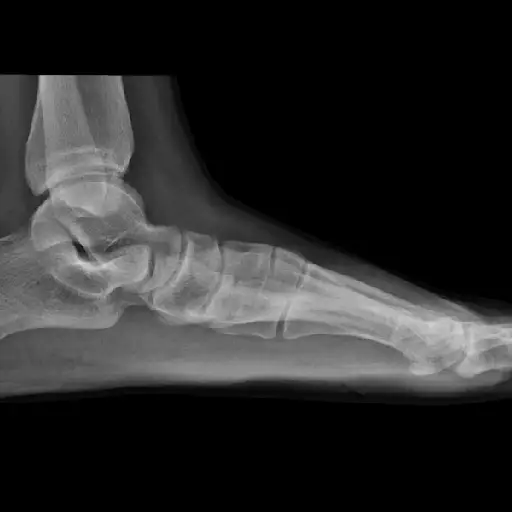

问题:拱痛

普通女性在50岁和60年代每年获得一半和半磅。即使是适度的增加的加重量也会影响脚部的拱门,因为顶部的额外重量等于下面的压力增加。拱门可以削弱,开始变平,甚至崩溃。具体而言,保持拱形的肌腱,后部胫骨肌腱,可以抑制或撕裂。这种痛苦的不适技术术语:Purtorar筋膜炎。

LifeStyle改变最小化体重增加将减轻脚的负担,但您也想立即解决任何拱形疼痛。“更容易解决的方式前撕裂发生,疤痕组织发展,“Reid博士警告博士。矫形器是控制有助于脚跟疼痛的力量的转向。站立或行走时,穿着僵硬的鞋跟也可以避免拱门。其他选择包括物理疗法(具有在家脚部锻炼)甚至干细胞注射。也有手术。但幸运的是,没有它可以解决“90%的跖骨问题”,“里德博士说。